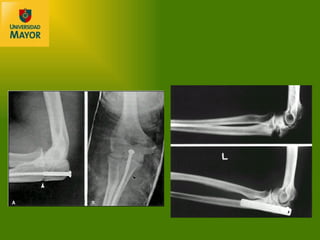

LESIONES LIGAMENTOSAS ASOCIADAS luxofractura de Galeazzi Fractura diafisiaria radio o antebrazo asociada a luxación radioulnar distal Signos radiográficos de compromiso RUD: Fractura base estiloides ulnar Aumento espacio articular en AP Incongruencia radioulnar en lateral Acortamiento radial  >5 mm

LESIONES LIGAMENTOSAS ASOCIADAS luxofractura de Monteggia Considerar lesiones equivalentes a las clásicas de Bado: Luxación anterior cabeza radial  + fractura diafisiaria ulnar angulada a anterior. Equivalente: fractura diafisiaria ulnar  + fractura c úpula o cuello radial Luxación posterior o posterolateral cabeza radial  + fractura diafisiaria ulnar angulada a posterior. Equivalente: luxaci ón posterior de codo  + fractura diafisiaria ulnar + fractura cúpula o cuello radial Luxación lateral o anterolateral cabeza radial  + fractura metafisiaria ulnar proximal Luxación anterior cabeza radial + fractura diafisiaria tercio proximal antebrazo

Signos radiológicos de congruencia RUP: Línea axial por diáfisis radial y cabeza, debe alinearse con capitellum en ambas proyecciones Doble línea cabeza radial en proyección lateral, con antebrazo supinado

TRATAMIENTO ortop édico Sólo reservado para ulna aislada, bajo las siguientes condiciones: Dos tercios distales Descartar lesión ligamentosa asociada Angulación no mayor a 10° Desplazamiento  <50% Uso de brace funcional No requiere maniobras de reducción